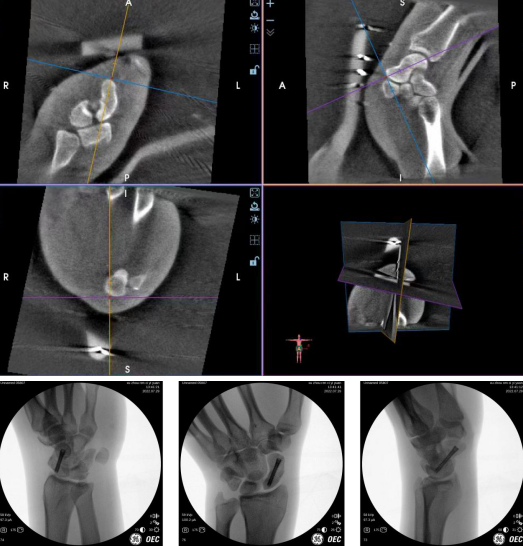

齐伟亚主任手术团队当天就为王先生进行了--“天玑骨科手术机器人导航下左腕舟骨骨折复位内固定术。”术中医生先用3D“C”臂机对其进行360°环扫,随后“机器人大脑”开始成像,骨折部位得以清晰呈现。通过传送图像、规划线路等设计,将导针精准的置入术中规划的位置,主刀医生通过导针的引导,拧入一枚Herbert加压螺钉,整个手术过程仅45分钟,且手术切口不足3毫米,仅有一个钉眼大小,不仔细看根本看不到,相比较传统手术刀口长,影响美观,机器人微创手术完美的规避了这一点。

手术切口